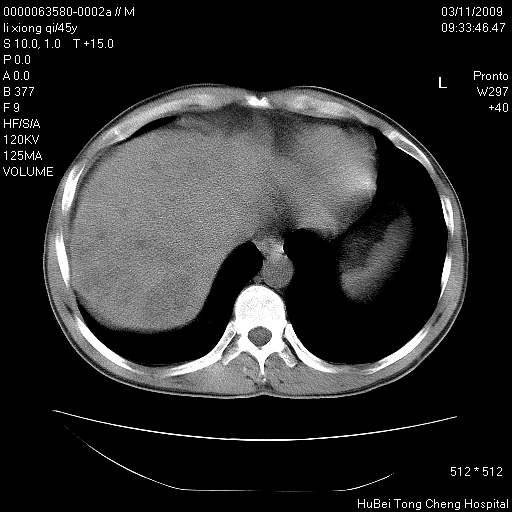

患者 男,45岁。胸痛,咳嗽伴痰中带血1月余。

临床诊断:肺结核?

胸部ct轴位平扫(层厚10mm,螺距1.5,重建间隔10mm),图像如下:

考虑肝癌肺转移